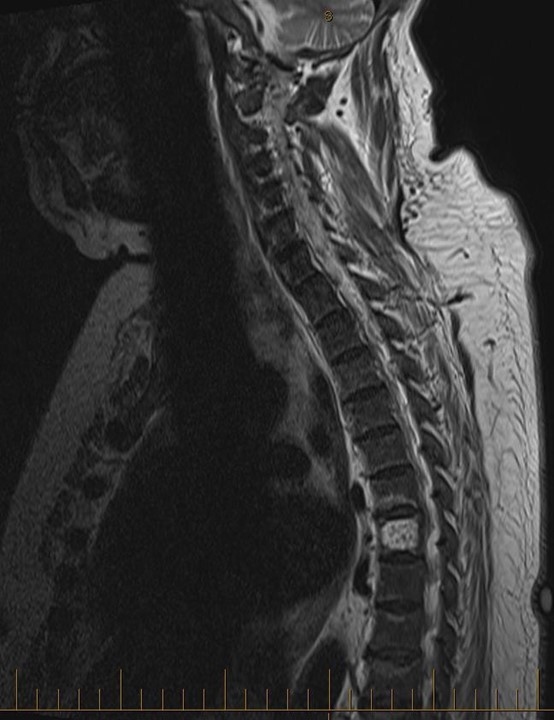

Given the persistent bone pain coupled with a very high TALP, it was decided to complete the workup to further characterise her bone disorder. An alkaline phosphatase electrophoresis was performed, which confirmed that 97% of the TALP was of bone origin. Plain radiographs were also performed. Radiographs of her knees and hands were suggestive of hyperparathyroidism, with subperiostal resorption (Figure 2). The skull radiograph demonstrated a salt and pepper skull (Figure 2). Finally, radiographs of her spine showed a rugger jersey spine (Figure 4), a brown tumor at D12, as well as multiple vascular calcifications. Magnetic resonance imaging of her spine confirmed the presence of and better characterised the brown tumor (Figure 5). A bone scan ruled out Paget’s disease. It is to be noted that she did not undergo a bone biopsy due to lack of accessibility.

Figure 5: Magnetic resonance imaging of the patient’s spine, showing a brown tumor at D12